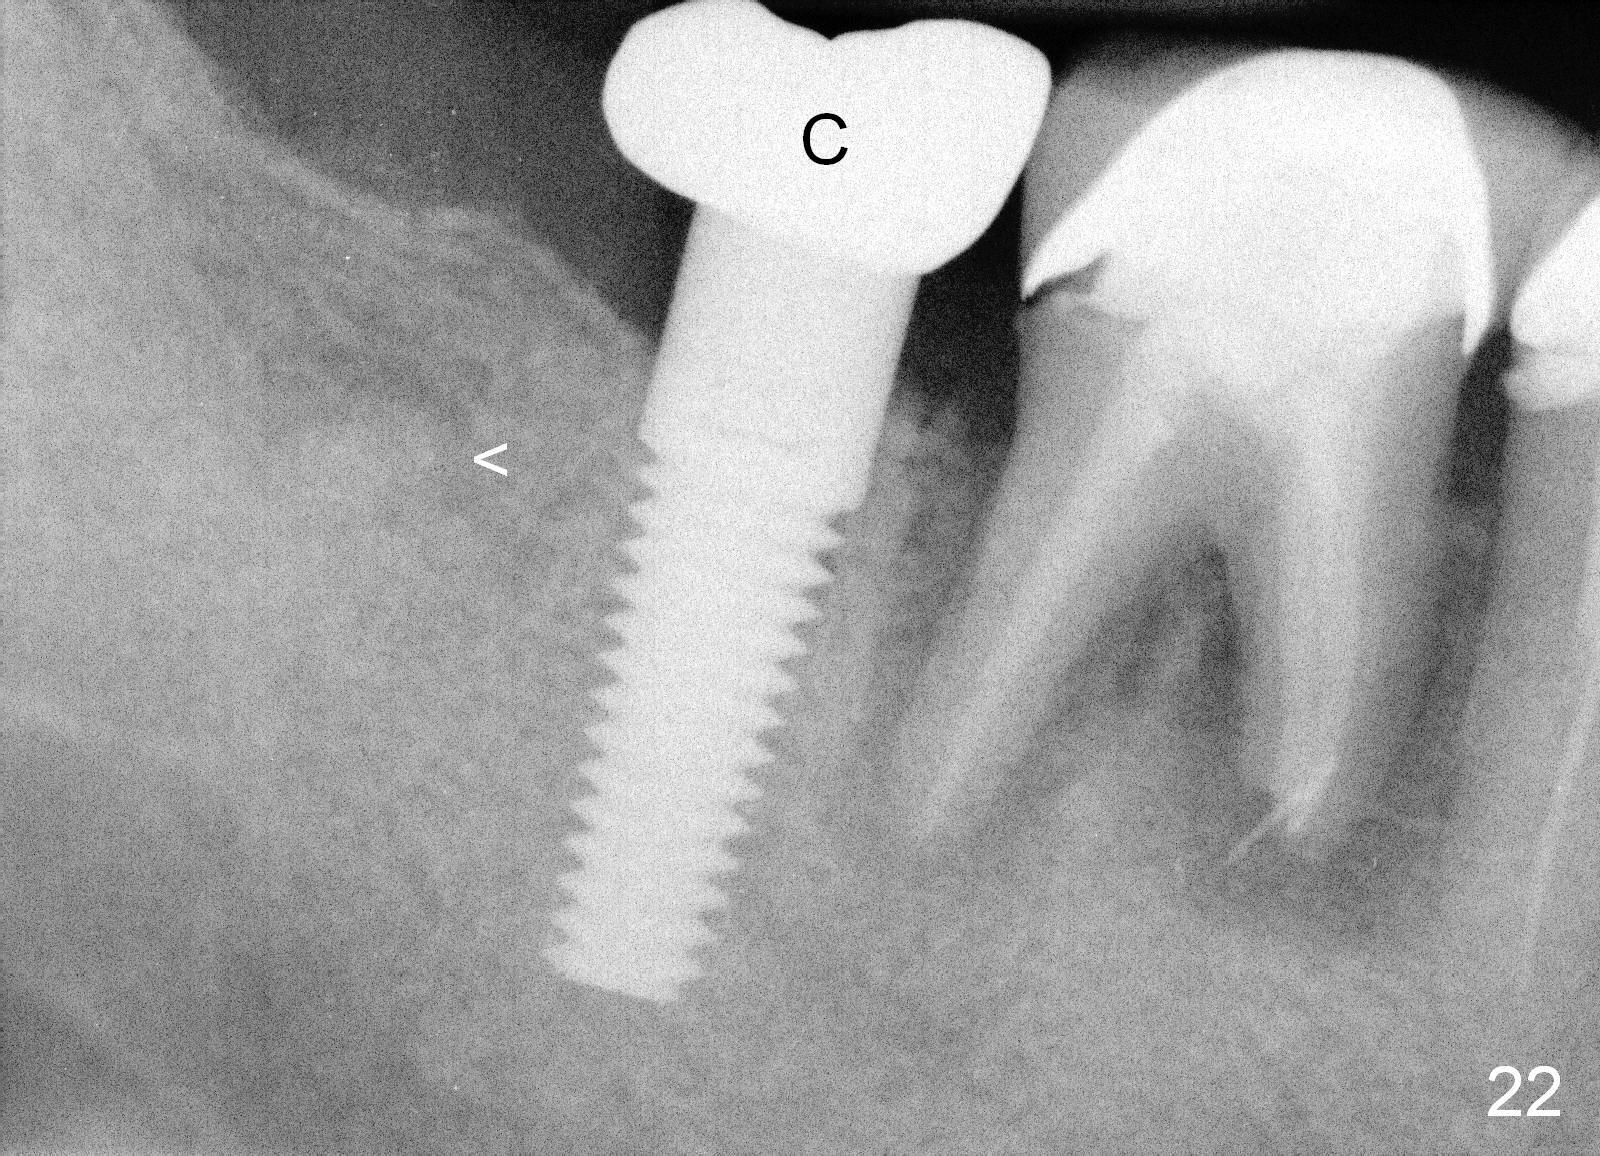

Four months postop, there is a sign of osteointegration (Fig.16 <). Graft particles migrate to the surface of the mucosa (Fig.17 <). A healing cuff is placed over the implant for preparation of restoration (Fig.18 H); graft particles are removed (<). Due to insurance issue, the restoration is yet to finish by 6 months postop (Fig.19 C: healing cuff); the cystic lesion appears to have been decreased concentrically (*). The bone density in the former cyst area continues to increase 14 and 32 months postop (Fig.20 A: abutment; Fig.22). Small piece of bone graft (<) is being extruded distobuccal to the #31 crown (C) asymptomatically 15 and 32 months postop (Fig.21,22).